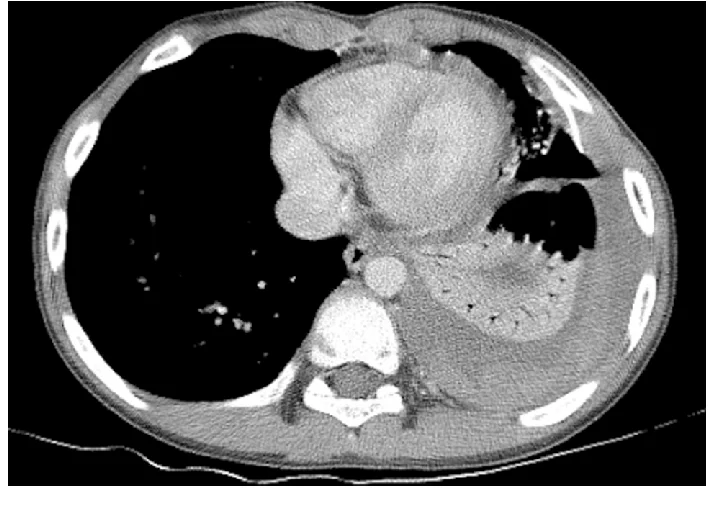

Метастази

Рак легень може поширюватися за межі первинного вогнища, утворюючи метастази.

На КТ радіолог оцінює:

- наявність додаткових вузлів у легенях,

- ураження інших органів (печінки, наднирників тощо),

- зміни в кістках.

Метастази можуть виглядати як множинні округлі утворення різного розміру. Їх виявлення є важливим для визначення стадії захворювання та вибору тактики лікування.

Лімфаденопатія

Ще один важливий показник — лімфаденопатія, тобто збільшення лімфатичних вузлів.

Лімфатичні вузли розташовані в грудній клітці та виконують захисну функцію. При онкологічних процесах вони можуть збільшуватися через поширення пухлинних клітин та реакцію імунної системи.

На КТ лікар оцінює розмір лімфатичних вузлів, їхню структуру та локалізацію. Збільшені вузли можуть бути ознакою поширення захворювання.